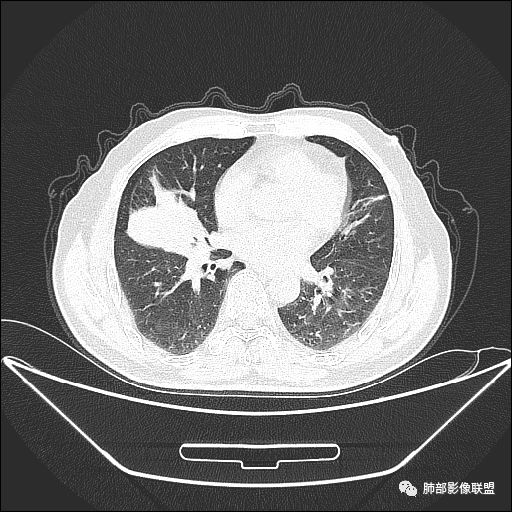

住院4天后行胸部增强CT

静脉期

吴婧老师和南边老师都对该病例进行了深入分析。从支气管管壁的增厚,支气管狭窄后扩张,支气管粘液栓,病灶形态,到病灶不均匀强化及坏死彻底,到周边病灶及肺组织空气的潴留,加之纵隔内淋巴结肿大伴钙化等等,都支持慢性炎性病灶,尤其是结核。

现在小编来增加一个炎性另一个征象,是我们王兆宇老师原创的----就是墨西哥仙人掌征。

墨西哥仙人掌征---结核        影像上结核灶,粗大的均匀枝干,推测是支气管囊状扩张引起的,在非支气管区,形成圆形坏死囊群;如果这些坏死比较稀薄,又遇到扩张支气管,就会形成粗大的“墨西哥仙人掌”。结核引起的支气管近端炎症纤维化,可以造成支气管阻塞,从而将干酪样坏死物封堵在管腔内。仙人掌主干内部应该是干酪为主,稀薄的,具有流动性,时间久了会出现钙化。

结核坏死与鳞癌鉴别有一点是结核坏死没有方向性,鳞癌有。鳞癌靠近支气管近端部分,血供容易维持,不易坏死,所以坏死靠外侧。而结核干酪样坏死,把一定体积的流动性坏死物,包裹起来,什么形状最省料?坏死物包裹,表面积最省的自然是圆球形,而遇到支气管,坏死物一多,就把支气管撑大了。包裹物是就地取材,扩张的支气管就成了包裹结构。